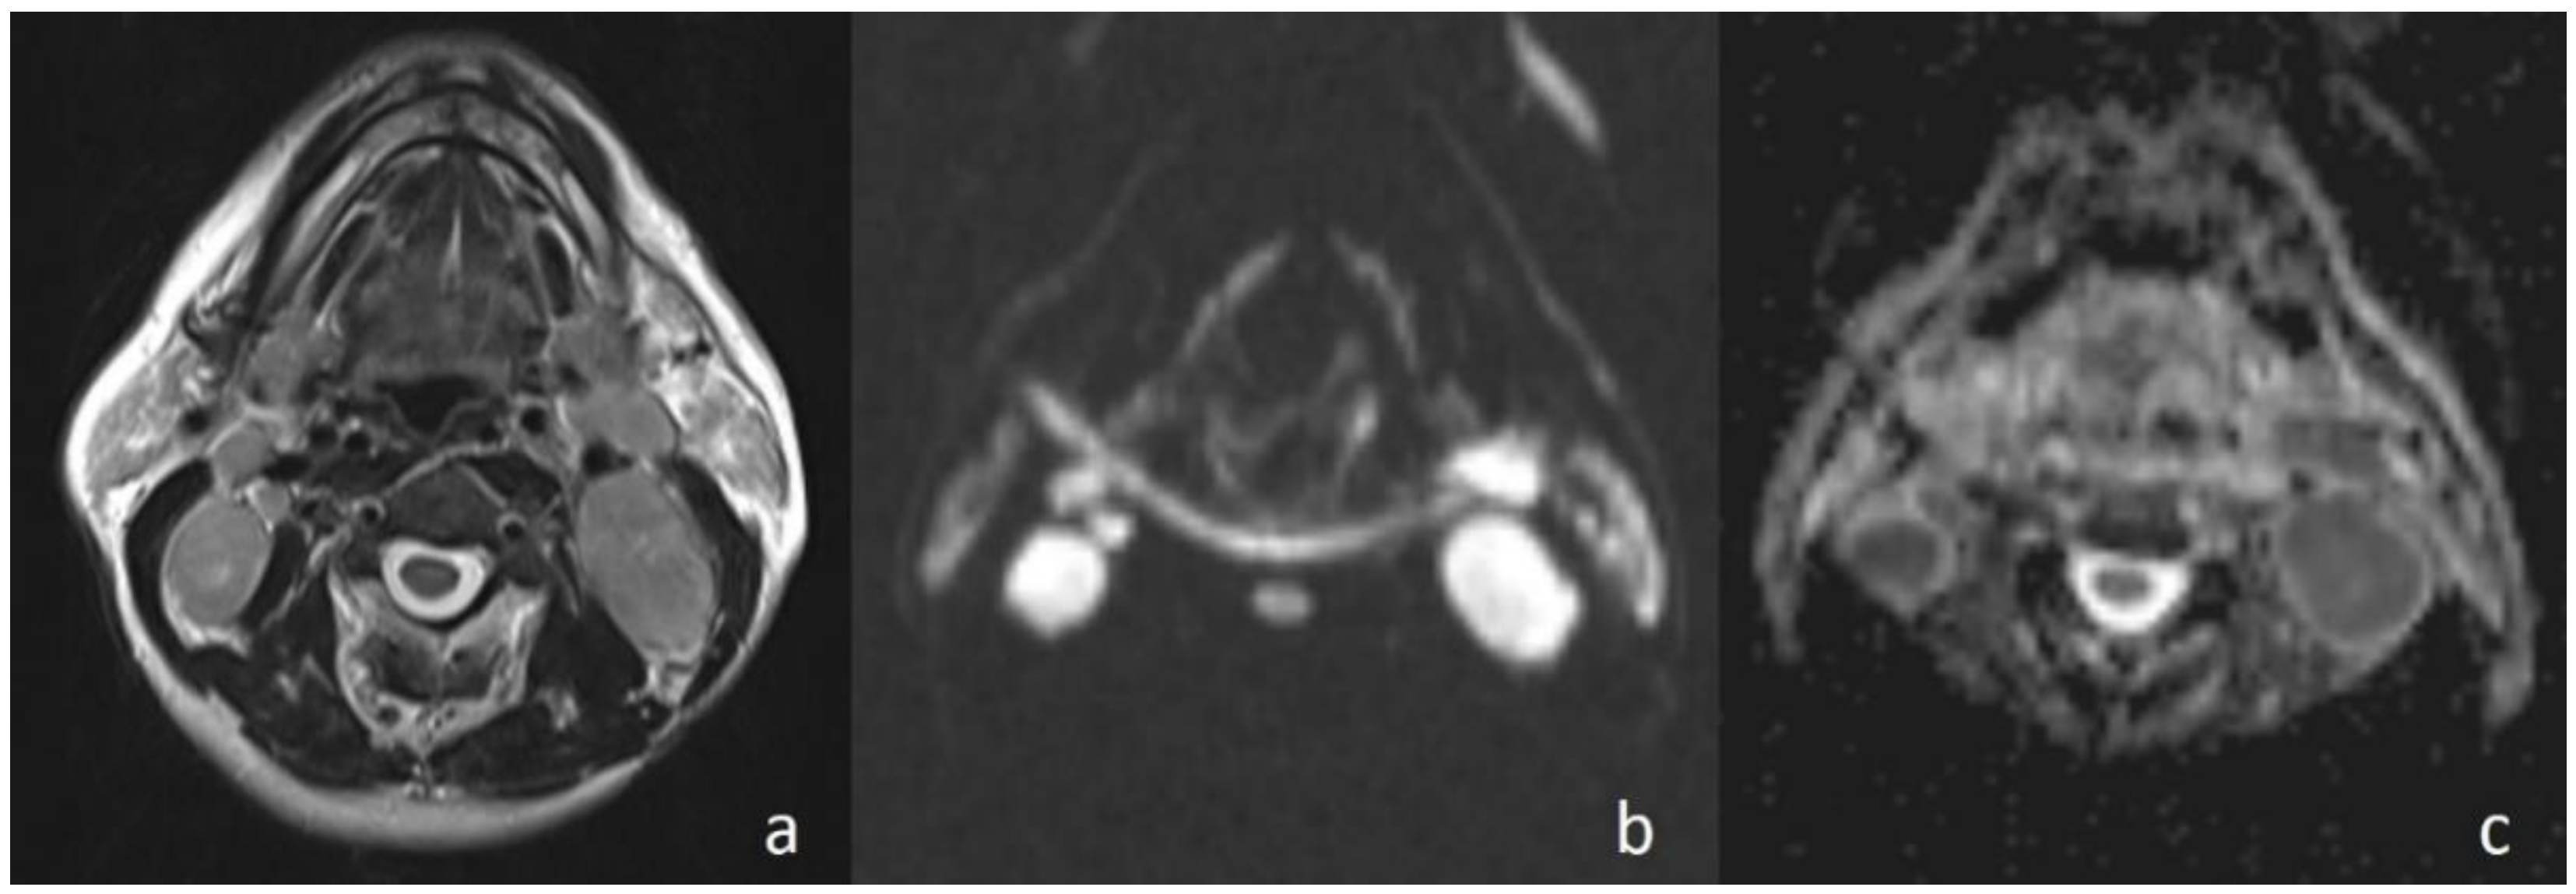

Figure 4. Second branchial cleft cyst. (a) Axial T2WI shows a unilocular cystic mass in the left carotid space; (b) the lesion shows low signal intensity on DWI; and (c) the lesion is hyperintense on the ADC map (ADC value of 2.02 × 10−3 mm2/s).

Apparently higher ADC values for benign cystic masses may be expected because of the relatively freer mobility of water protons in the fluid. In the current study, cystic masses were not grouped separately due to low numbers. However, consistent with previous studies, the mean ADC value of three cystic masses (Figure 4) (1.98 × 10−3 mm2/s) was higher than that of other benign solid masses (ADC = 1.48 × 10−3 mm2/s). In addition, the differences in ADC values among cystic masses could be explained by the different protein concentrations. A high protein level restricts the movement of water molecules by increasing the viscosity [15].